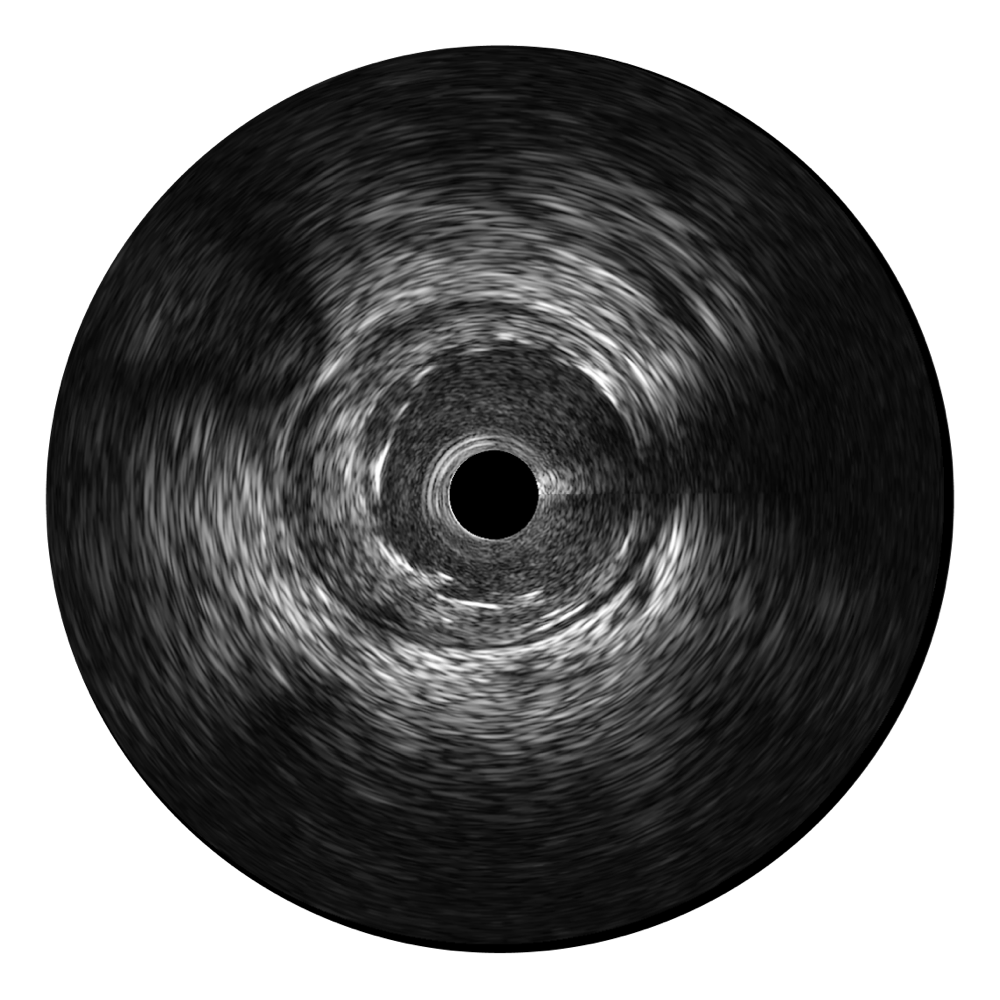

传统IVUS图像

对比传统IVUS导管成像,milan米兰宽频IVUS图像的近场支架梁显影更细腻,远场中膜外血管仍清晰可辨,兼顾远中近,兼顾分辨力与穿透深度